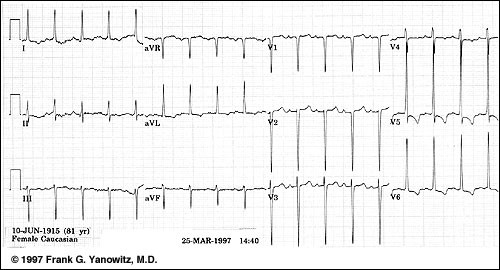

L.N. is a 49-year-old white woman with a history of type 2 diabetes, obesity, hypertension, and migraine headaches. The patient was diagnosed with type 2 diabetes 9 years ago when she presented with mild polyuria and polydipsia. One year ago, microalbuminuria was detected on an annual urine screen, with 1,943 mg/dl of microalbumin identified on a spot urine sample. L.N. comes into the office today for her usual follow-up visit for diabetes. Physical examination reveals an obese woman with a BP of 154/86 mmHg and a pulse of 78 bpm. ECG

Calculate The Sokolow-Lyon index and identify heart axis

Варианты ответов

- more than 35 and left axis deviation

- more than 25 and left axis deviation

- more than 35 and right axis deviation

- more than 25 normal heart axis

Вопрос 3

CHOOSE CORRECT STATMENT FOR THE GIVEN IMAGE

- POSITIVE R WAVE IN I AND NEGETIVE S WAVE IN AVF INDICATE LEFT AXIS DEVIATION

- POSITIVE R WAVE IN I AND POSITIVE S WAVE IN AVF INDICATE LEFT AXIS DEVIATION

- POSITIVE R WAVE IN I AND NEGETIVE S WAVE IN AVF INDICATE RIHGT AXIS DEVIATION

- ALL MENTIONED ARE CORRECT

FIND DIFFERENCES BETWEEN GIVEN ECG AND ATRIAL FLUTTER

- R-R INTERVAL IS IRREGULAR

- LONG QT INTERVAL

- NORMAL P WAVE

- DURATION OF QRS COMPLEX IS MORE THAN 0.10 SEC